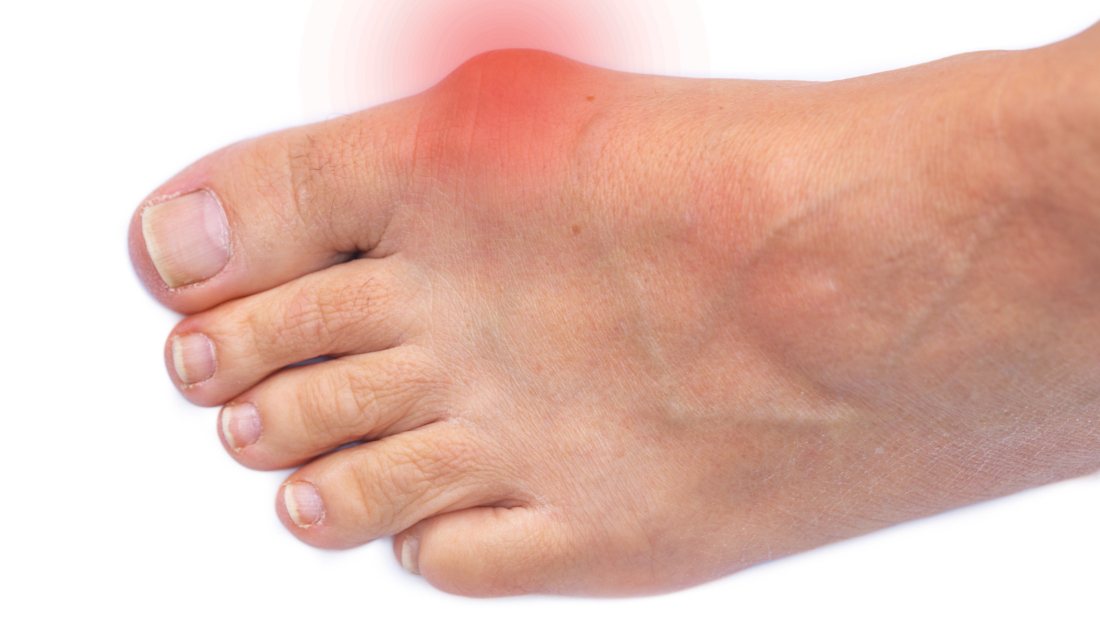

Ayak parmakları, özellikle ikinci, üçüncü ve dördüncü parmaklar bükülerek bir pençe görünümü alır. Parmaklar yukarı doğru kalkar ve eklemler bükülü kalır. Parmaklardaki bükülme, özellikle yürürken veya ayakkabı giyerken ağrıya neden olabilir. Bu ağrı, genellikle eklemlerde ve parmak uçlarında hissedilir. Parmakların bükülü durması, ayak parmaklarının uçlarında ve eklemlerde sürtünmeye neden olur, bu da nasırların oluşmasına yol açabilir. Ayrıca, ayak mantarına eğilim artabilir. Pençe parmak hastalığı, ayağın dengesi üzerinde olumsuz etkiler yaparak yürümeyi zorlaştırabilir. Zamanla parmaklardaki bükülme sertleşebilir ve bu durum, parmakların normale döndürülmesini zorlaştırabilir. Genellikle ayakkabı seçimi, kas zayıflığı veya nörolojik problemler nedeniyle gelişebilir. Tedavi egzersiz, ortopedik ayakkabılar veya ileri vakalarda cerrahi müdahale ile yapılır.

Ameliyat veya konservatif tedavi sonrası, kas gücünü ve esnekliği geri kazanmak için fizik tedavi önerilir. Egzersizler düzenli olarak yapılmalı ve doktorun talimatlarına uyulmalıdır. Operasyon sonrası dikişlerin bakımı hijyenik bir şekilde yapılmalı. Doktorun önerdiği pansumanlar düzenli olarak uygulanmalıdır. Enfeksiyon belirtilerine karşı dikkatli olunmalıdır. Parmakları zorlamadan dinlenmek, iyileşme sürecinde önemlidir. Ağır aktivitelerden kaçınmalı ve iyileşme tamamlanana kadar parmaklar korunmalıdır. Düzenli doktor kontrolleri, iyileşme sürecinin takibi açısından önemlidir. Herhangi bir komplikasyon durumunda erken müdahale sağlanabilir. İyileşme sürecinde sağlıklı bir beslenme ve yeterli su tüketimi, vücudun onarım sürecine katkıda bulunacaktır. Bu noktalara dikkat edilmesi, tedavi sonuçlarını olumlu yönde etkileyerek daha hızlı bir iyileşme sağlayabilir.